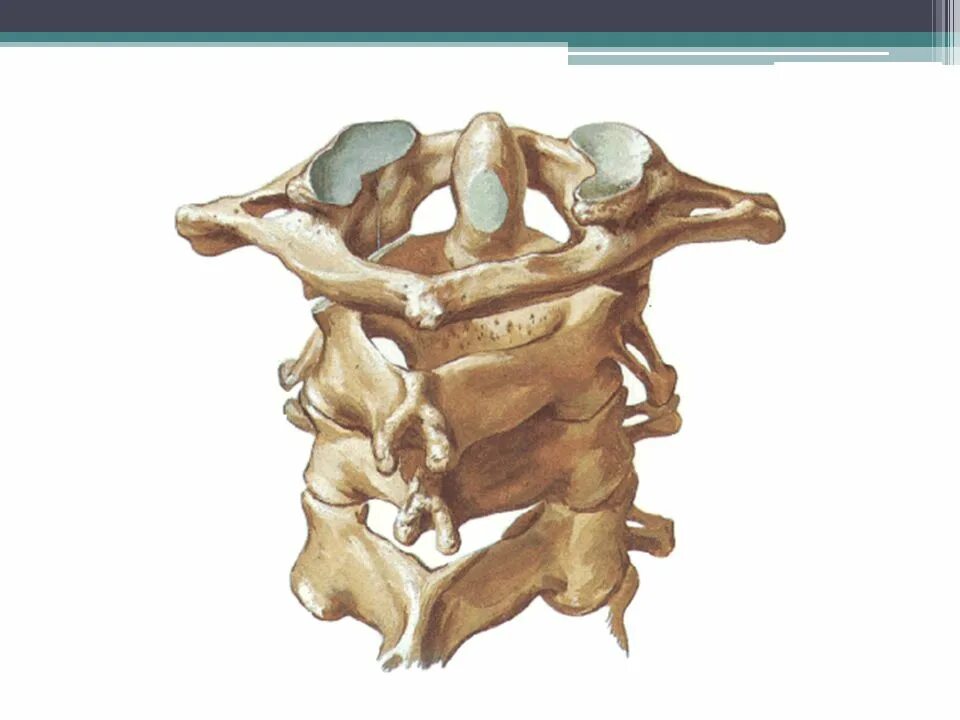

Dens axis